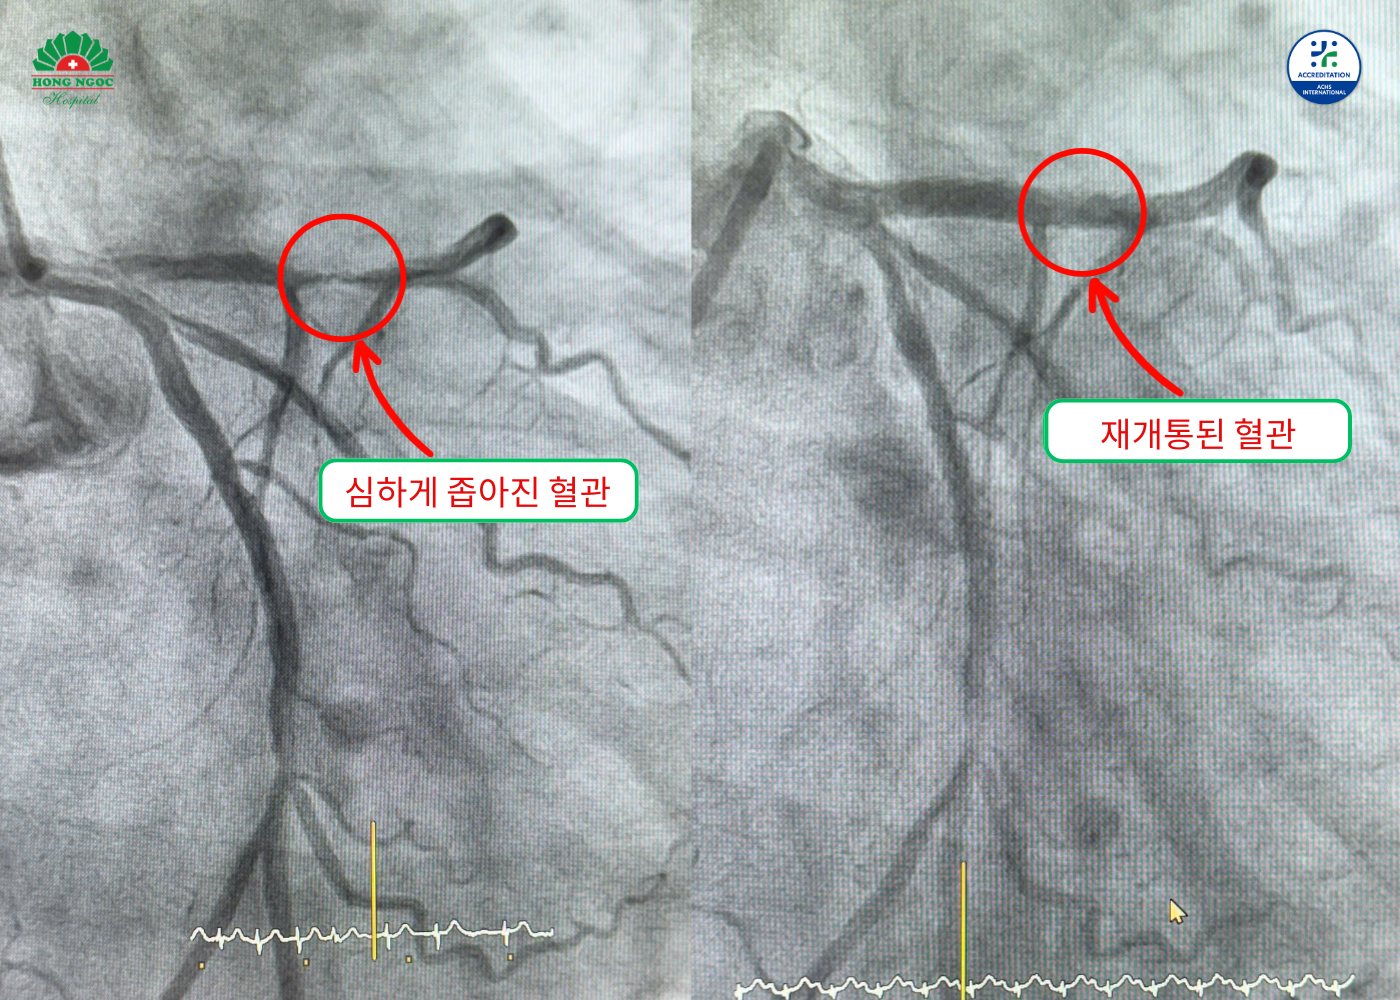

관상동맥 조영술 결과, 환자는 좌전하행동맥 근위부(심장을 먹여 살리는 주요 동맥 분지)가 거의 완전히 막혀 있는 것으로 나타났습니다. 또한, 우관상동맥도 약 70% 협착되어 있어 광범위한 심근 허혈 위험을 높였습니다. 환자는 여러 혈관에 손상을 입었으므로 의료진은 중재 시술을 결정했습니다. 의료진은 좌전하행동맥 부위에 약물 방출 스텐트를 삽입했습니다. 스텐트는 혈관 내경에 맞는 크기로 신중하게 선택되었습니다. 풍선 확장술은 압력을 엄격하게 조절하며 진행되었습니다. 이는 혈류를 확장하고 혈관벽 손상을 최소화하는 데 도움이 됩니다. 이러한 중재 방법은 찌엔(Chien) 씨처럼 출혈 위험이 높은 환자에게 특히 중요합니다.

환자의 관상동맥 시술 전후 영상